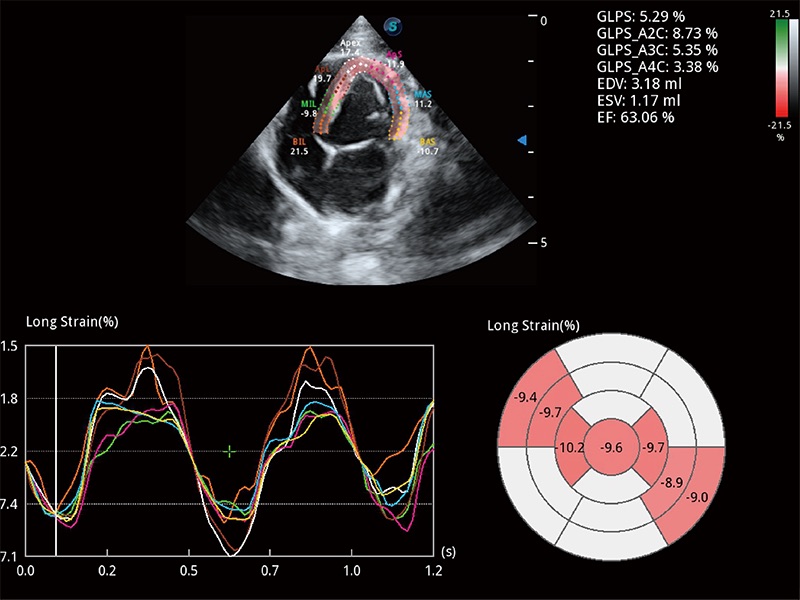

ProPet 80 配备了丰富的心脏探头群、先进的成像技术和专业的心脏测量工具,可帮助动物医生为不同体型和生理结构的动物提供心脏和心肌功能的全面评估。

通过心肌识别技术与二维斑点追踪技术相结合,对心脏的超声图像进行量化分析。计算心肌17个节段的应变、应变率、速度、位移等,并通过牛眼图的形式进行呈现。

能够基于左心室壁追踪和辛普森法,自动计算射血分数,支持多个可移动点描迹,与手动测量相比,极大节省了动物医生的时间和精力。